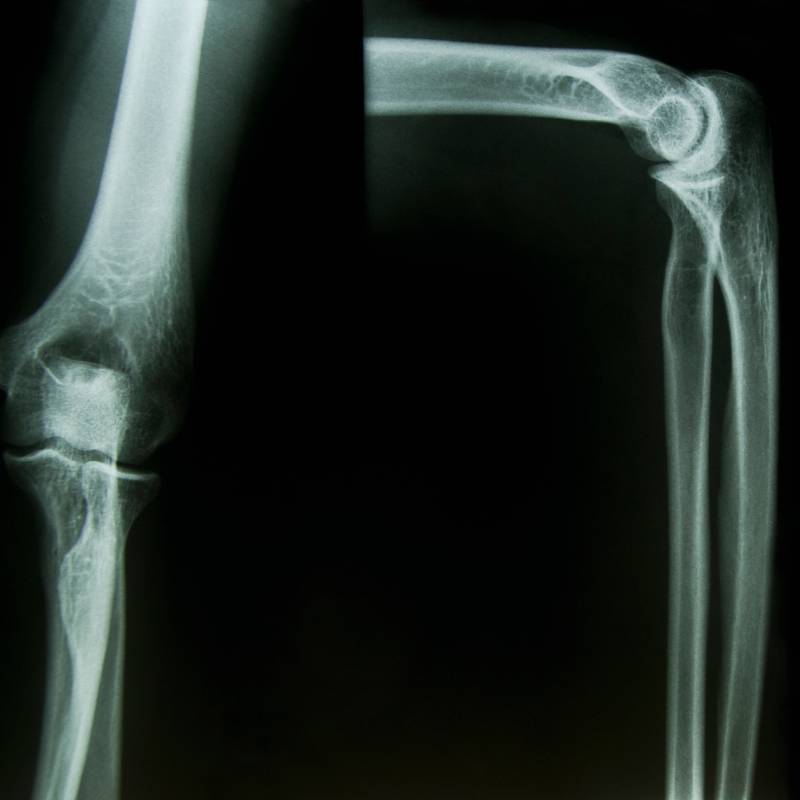

Sinar-X untuk memeriksa keadaan sendi siku.